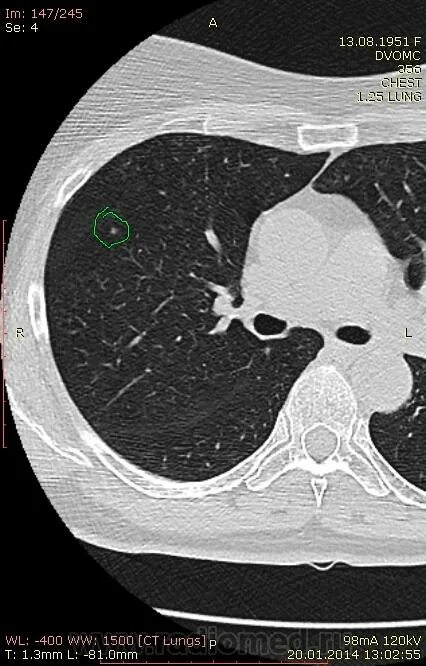

Фиброз кт